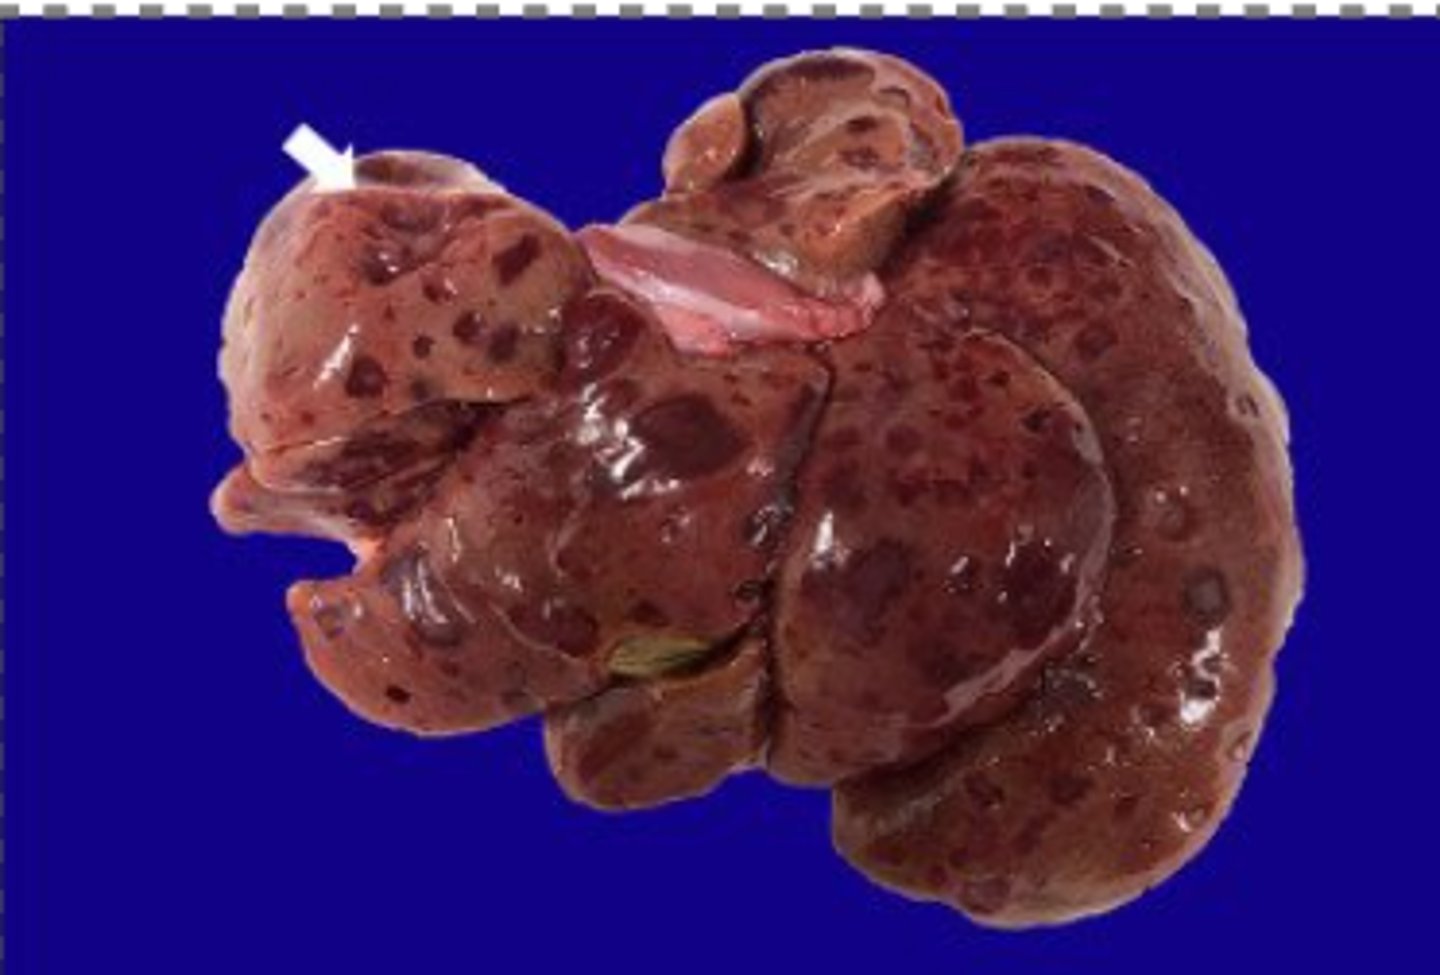

What has caused this gross appearance of this liver?

Chronic passive congestion

What has caused this gross appearance of this liver?

Chronic passive congestion

-classic Nut Meg liver

-brnahcing fibrosis + hepatocellular loss

What has caused this gross appearance of the liver?